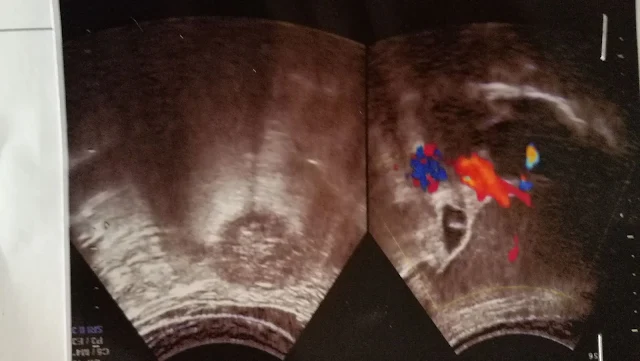

Minä sanelen tätä tekstiä koska en ole tietokoneella vaan matkalla puhelimeni mukanani. Kesäkuussa umpeutui jälleen viisumini Vietnamiin oli siis aika käydä maan ulkopuolella uusimmassa se. Maaliskuussa siis kolme kuukautta sitten kävin uusimassa viisumini Singaporessa samalla kun kävin silmälääkärissä. Nyt kesäkuussa päätin käydä jälleen Thaimaassa Bangkokissa kuten olen tehnyt monta kertaa aiemminkin. Vain pari päivää ennen aiottua matkaa minulle tuli ongelmia vatsan kanssa ajattelin että ruoan pala on takertunut suolistoon koska vatsani tuntui täydeltä ja tunsin kipua rinnan keskikohdassa ajattelin että se menee ohi itsestään mutta se ei mennyt vaan kipu oli aika voimakas ja tunsin itseni hyvin heikoksi siksi pyysin puolisoani viemään minut lääkäriin. Lääkäri tutki vatsaani ultraäänellä ja ilmoitti tuloksen minulla on sappikiviä.

Nyt sain selityksen sille oudolle tunteelle pienelle sivulle rinnassa joka minulla on ollut silloin tällöin. Se ei ole oikealla puolella vaan keskellä. Ehkä siksi sitä ei ole mielletty sappivaivat miksi vaan olen ajatellut että se on joko liikahappoisuutta tai sitten joku pieni tukos suolessa, ummetusta.

Nyt minulla oli lääkärintodistus, joten suostuin siihen etten voi lentää koska minulla mitattiin myös hyvin korkea verenpaine sain joitakin lääkkeitä ilmeisesti myös verenpainelääkettä. Minulla ei ole koskaan aiemmin ollut korkea verenpaine.

Kommentti syyskuussa 2025: Ehkä oli väärä diagnoosi väittää oireiden johtuneen sappikivistä. Ne olivat ehkä yksi syy, muttei se suurin. Uskoin tuota diagnoosia aina kesäkuulle 2025 saakka, jolloin hakeuduin kardiogolille rintakivun jatkuttua ja voimistuttua ja verenpaineen näyttäen korkeita lukemia. Tutkimusten jälkeen paljastui sepelvaltimotauti ja kaksi merkittävää tukossa sydämen valtimoissa.